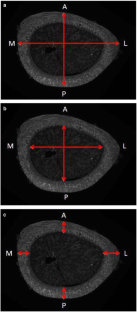

Scientific evidence has shown the nutritional importance of boron (B) in the remodeling and repair of cancellous bone tissue. However, the effects of the nutritional deficiency of B on the cortical bone tissue of the appendicular skeleton have not yet been described. Thus, a study was performed to histomorphometrically evaluate the density of osteocyte lacunae of cortical bone of mouse femora under conditions of nutritional deficiency of B and to analyze the effects of the deficiency on the biomechanical properties of mouse tibiae. Weaning, 21-day-old male Swiss mice were assigned to the following two groups: controls (B+; n = 10) and experimental (B−; n = 10). Control mice were fed a basal diet containing 3 mg B/kg, whereas experimental mice were fed a B-deficient diet containing 0.07 mg B/kg for 9 weeks. The histological and histomorphometric evaluations of the mice fed a B-deficient diet showed a decrease in the density of osteocyte lacunae in the femoral cortical bone tissue and the evaluation of biomechanical properties showed lower bone rigidity in the tibia.